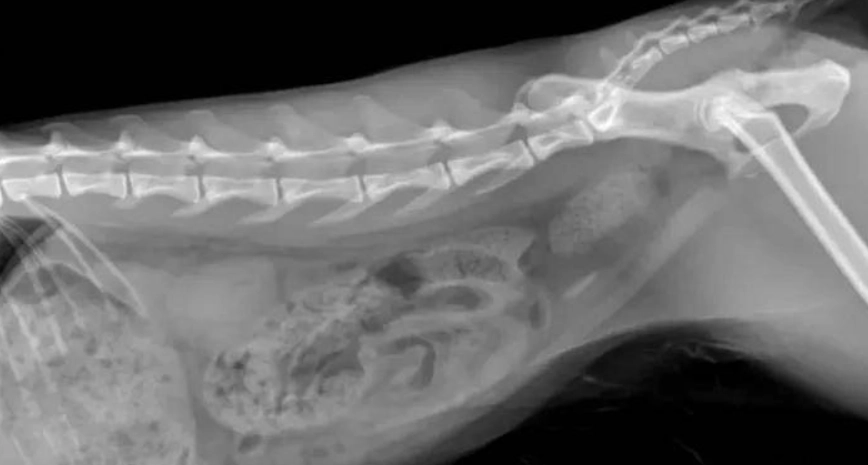

米米是五歲公貓,去年發現尿不出來,診斷是草酸鈣結石,緊急手術。以下是我們的護理日誌。